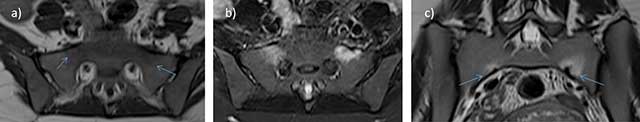

Figure 12

Inflammatory arthritis of sacroiliac joints in the postpartum: axial STIR a) and b) and frontal STIR c) MRI images show high signal intensity of the right and left joint space (*), subchondral bone (–>), and soft tissue (>) with no fluid collection.